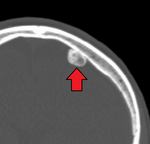

Type Name Sub-type Image

Non-cancerous Osteoma

Osteoid osteoma